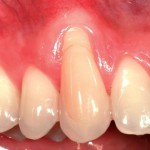

Trattamento estetico di una recessione gengivale

Riassunto

La regione cervicale degli elementi dentari può essere spesso interessata da abrasioni dentarie correlate a una concomitante recessione dei tessuti molli. Nel seguente articolo è presentato...